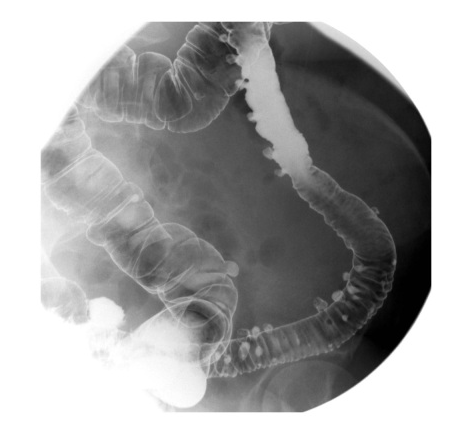

diagnosis

diverticulosis